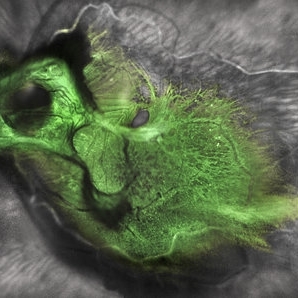

Tractional retinal detachment with macular hole in a 76-year-old female.

Photographer: John Golding BA, Vitreous Retina Macula Specialists of Toronto, OCTane Imaging Lab

Imaging device: Multicolor fundus photo taken on the Spectralis OCT2 (Heidelberg Engineering GmbH).

Condition/keywords: macular hole, Multispectral imaging, tractional retinal detachment